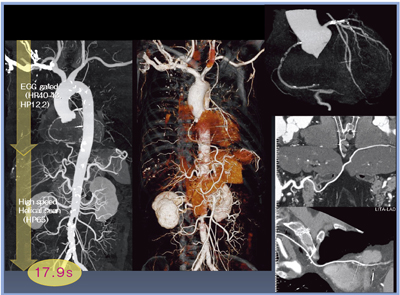

VHPでは,心電図同期のONからOFFへの切り替え時間が不要になったため,息止め時間が平均17秒前後にまで短縮され,CT値も均一になった。画像をつくる手間も減り,スタッフの業務軽減にもつながっている。

動脈グラフト併用CABG術後に対し,VHPで撮影した症例を示す(図10)。大動脈全体が評価できるほか,心電図同期ONとOFFの境界をまたぐように走行する胃大網動脈グラフトも,段差がないだけでなく,native RCAとの吻合部も含めて明瞭に描出され,良好な画質で評価できるようになった。

図10 VHPを用いたCABG術後の冠動脈と大動脈の同時評価